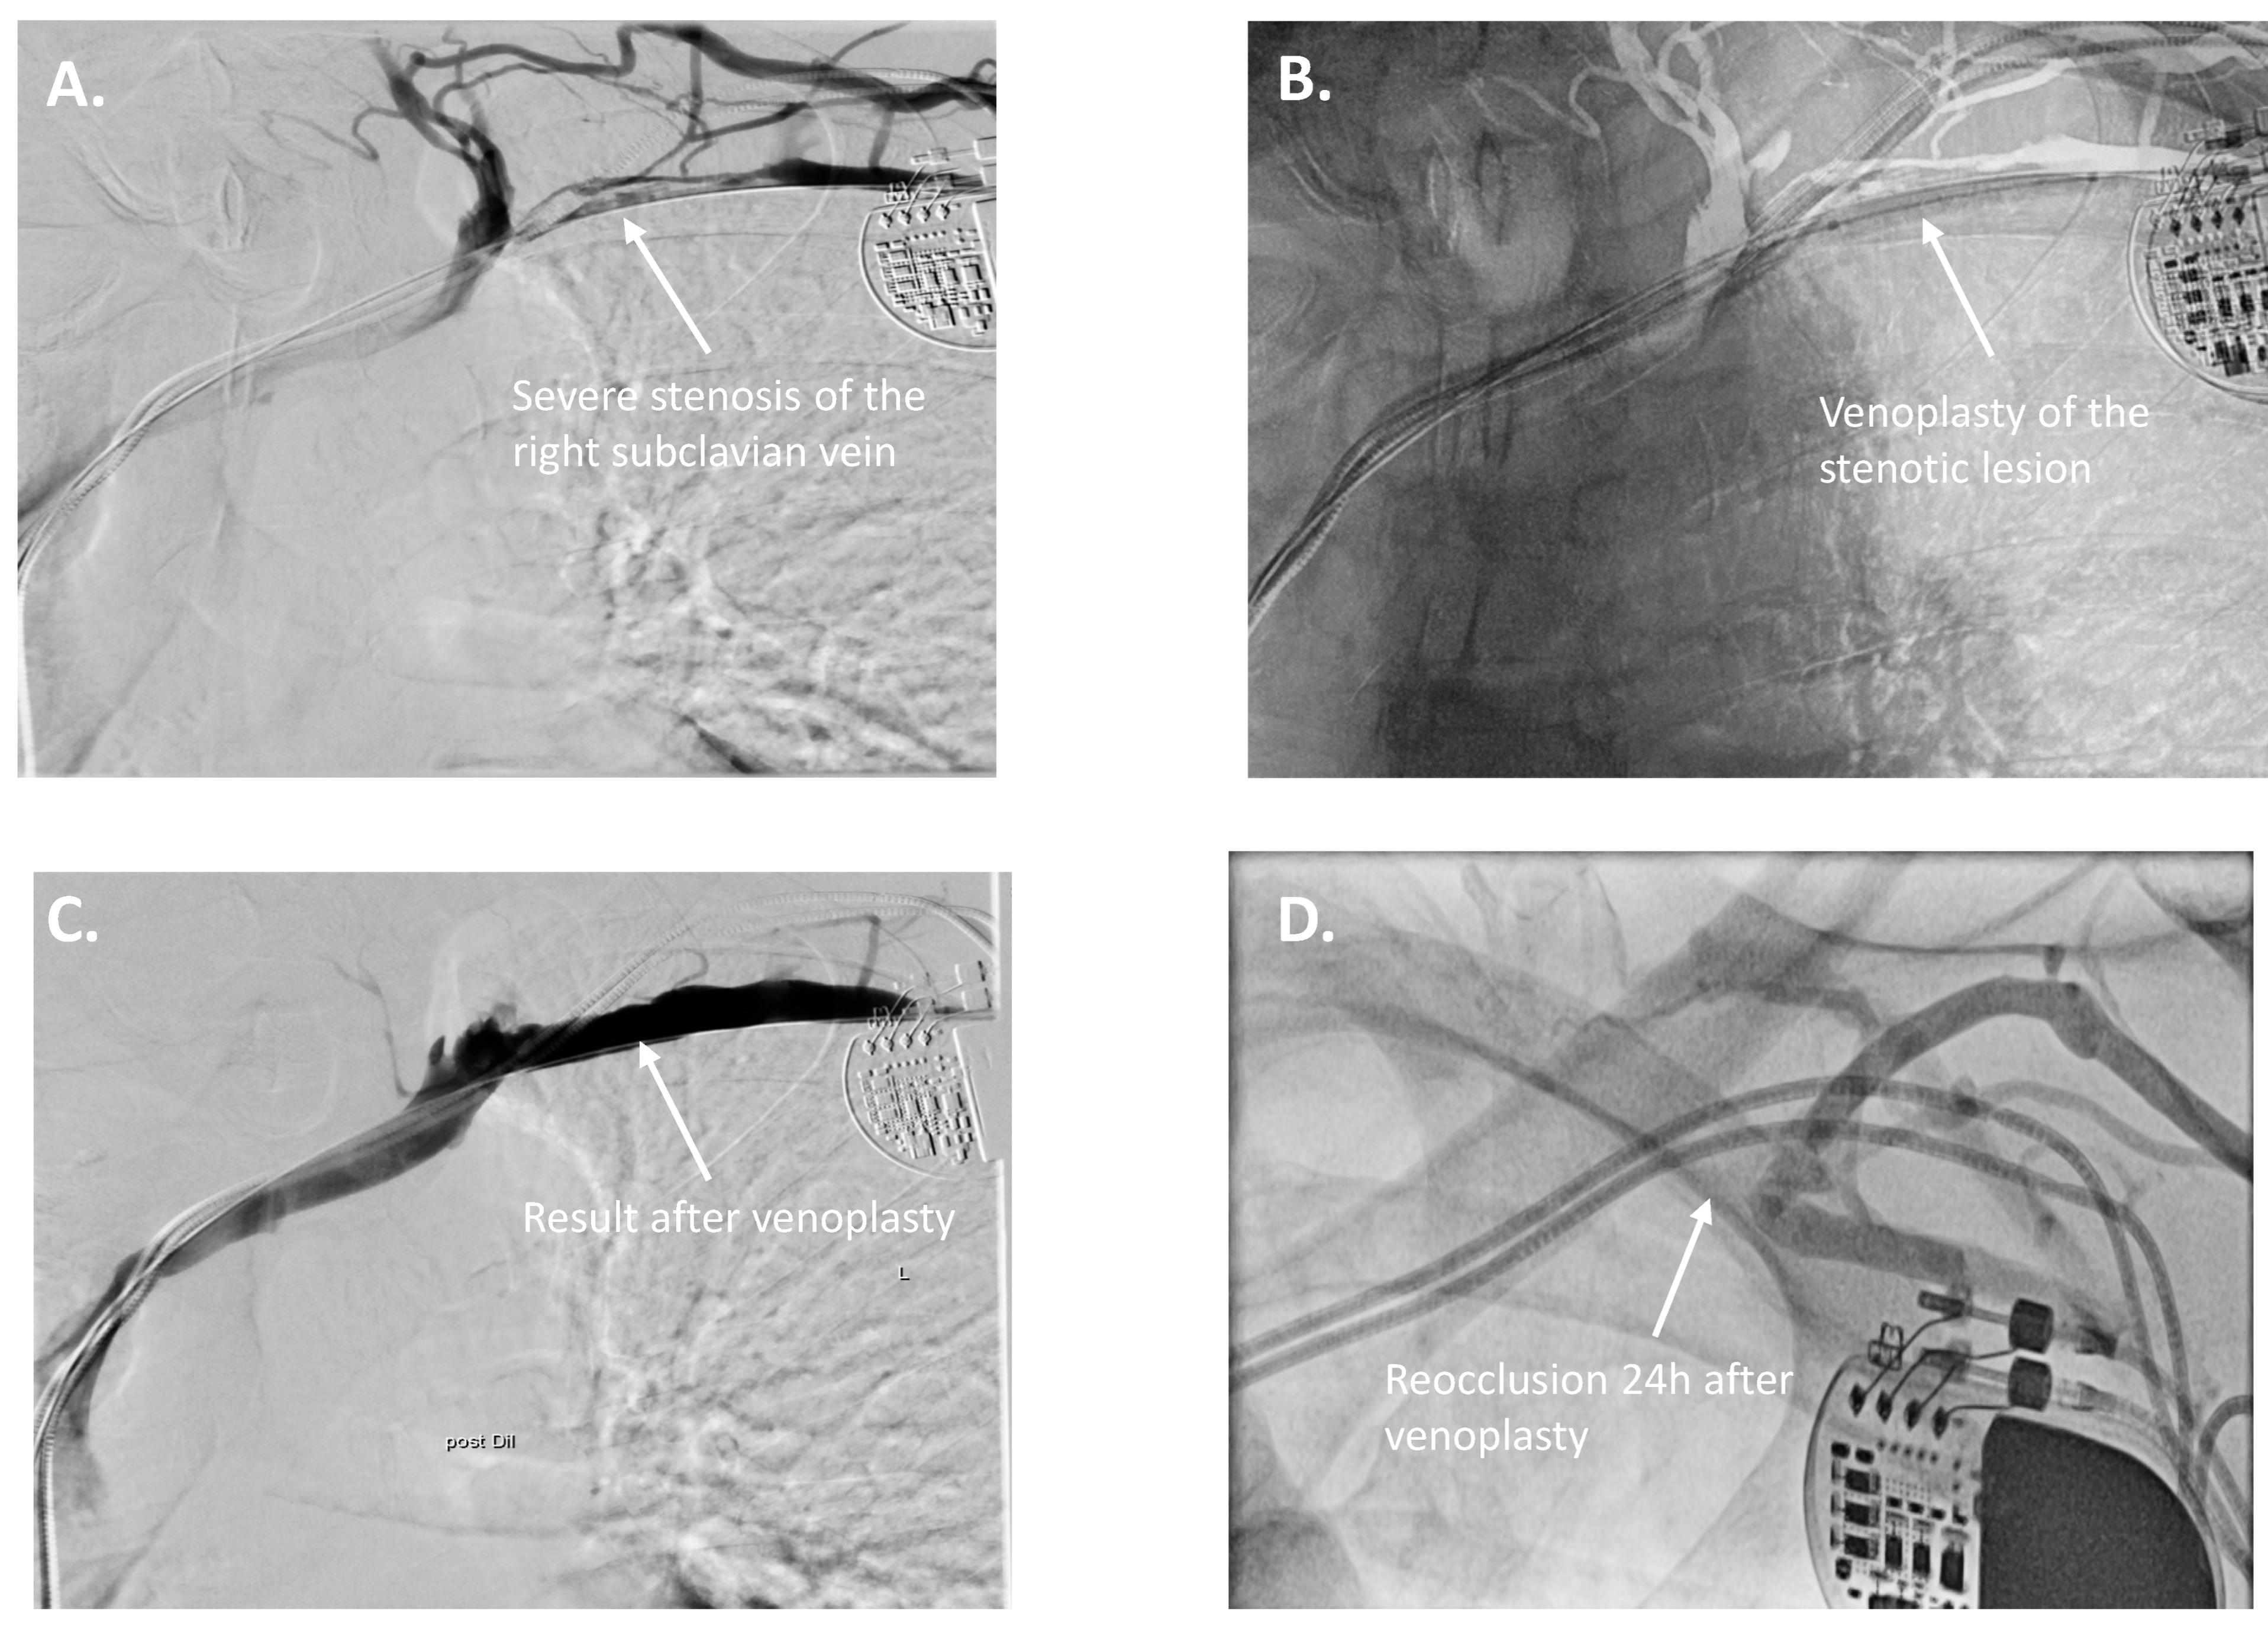

| 7 | 2-chamber pacemaker → CRT-D upgrade | LVEF deterioration, increased ventricular pacing | Right subclavian vein stenosis | Right subclavian PTA via axillary/brachial vein | CRT-D upgrade successful |